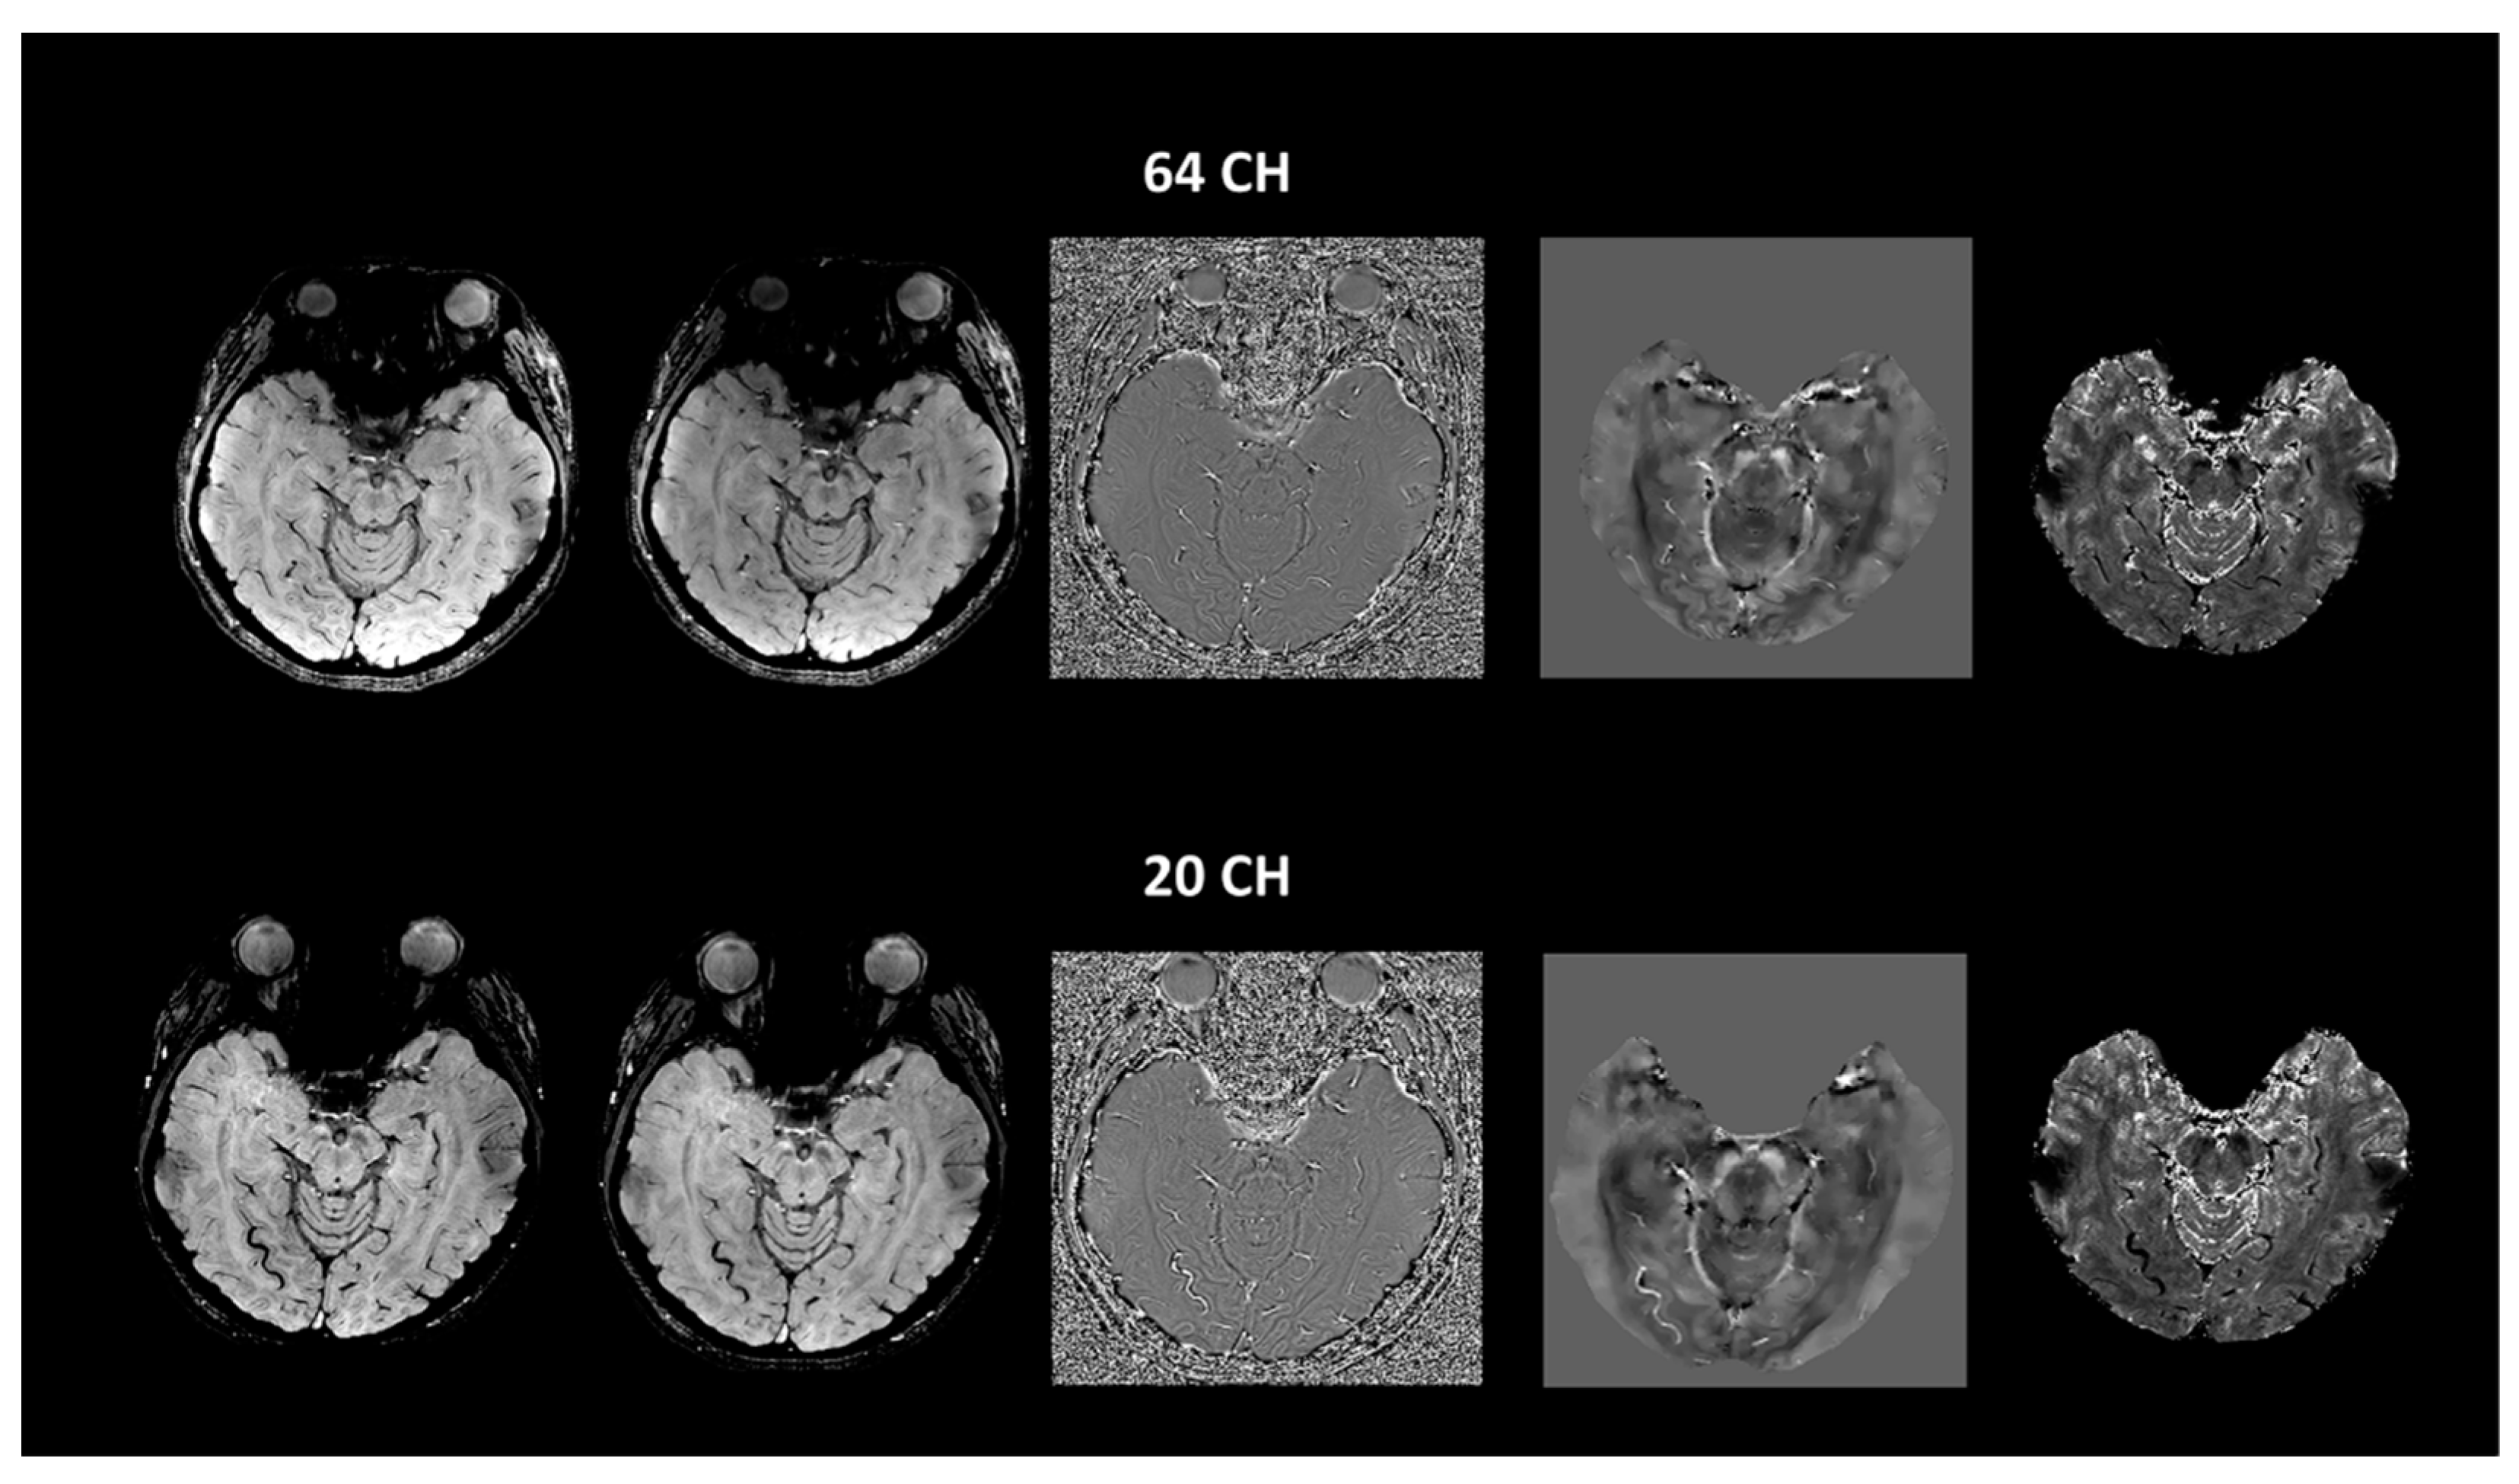

| SWIave | Magave | Phaave | SWI | Mag | Pha | QSM | T2* | |||

|---|---|---|---|---|---|---|---|---|---|---|

| 64 CH | Older | Mean (std) | 2.75 (0.22) | 2.03 (0.23) | −0.55 (0.23) | 1.99 (0.32) | 1.67 (0.29) | −0.44 (0.18) | −0.80 (0.39) | 1.80 (0.44) |

| Young | Mean (std) | 2.52 (0.28) | 1.77 (0.37) | −0.62 (0.35) | 1.67 (0.36) | 1.39 (0.34) | −0.46 (0.25) | −0.57 (0.34) | 1.47 (0.49) | |

| 20CH | Young | Mean (std) | 2.58 (0.30) | 1.82 (0.30) | −0.60 (0.24) | 1.70 (0.29) | 1.41 (0.29) | −0.47 (0.20) | −0.61 (0.32) | 1.49 (0.36) |